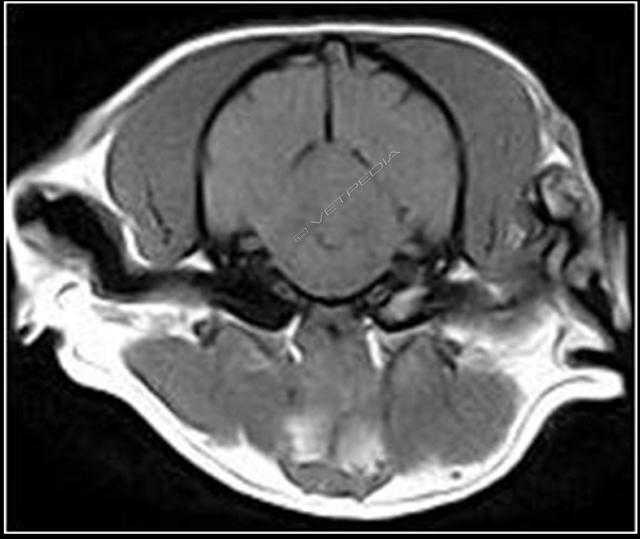

La più comune causa di patologia vestibolare periferica nei soggetti anziani è la malattia vestibolare idiopatica benigna (IBVD, Idiopathic Benign Vestibular Disease). Questa patologia può verificarsi in cani e gatti di qualsiasi età, ma nel cane l’età media d’insorgenza è 12,5 anni, pertanto viene spesso indicata anche con il nome di Sin...